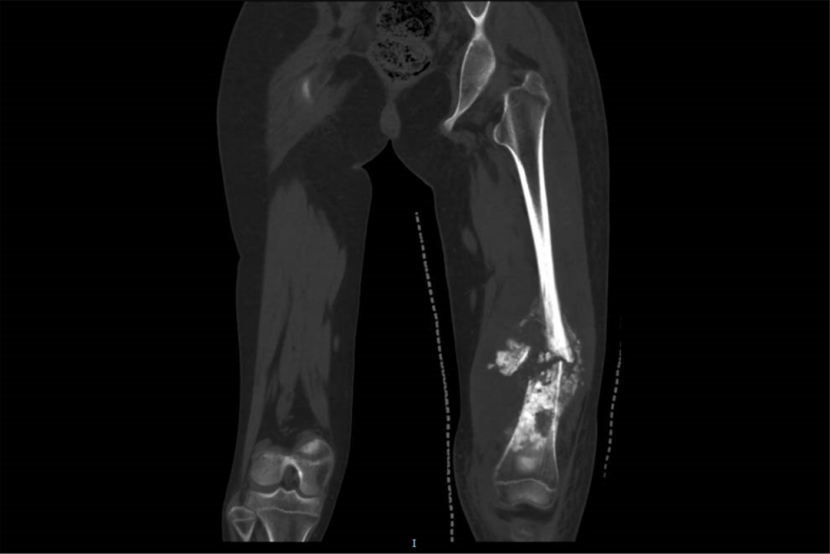

这是小鱼的术后X线影像

3D打印+可延长假体,精准重建护航未来成长

上个月,在充分准备的基础上,王克及其团队为小鱼实施了“肿瘤整块式切除+组配式半限制关节假体置换术”。术中利用3D打印截骨导板精确切除病变股骨组织,并细致分离肿瘤与周围重要血管神经的粘连,成功保留了胫骨骨骺生长板。植入的个体化肿瘤型人工关节假体外侧专门设计有可延长模块,为患儿未来生长发育预留了微创调节的技术空间,避免了因肢体不等长而进行的多次翻修手术。

术后仅两周,小鱼便可在支具辅助下尝试负重行走。接下来,他还将完成后续化疗及系统性康复训练,逐步恢复肢体功能。